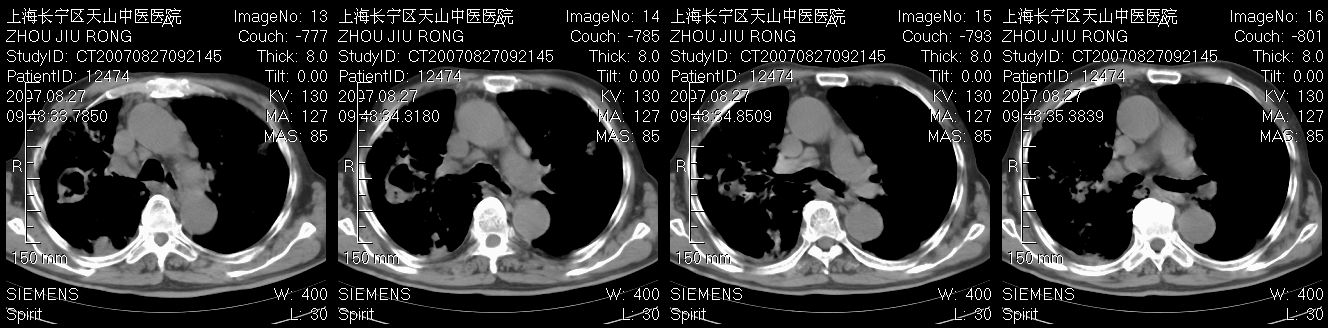

以下是引用zjzjr在2007-8-30 21:47:00的发言:[br]双肺弥漫性结节状、斑片状影,部分形成空洞,病灶以双肺上叶为著(符合结核发病部位),纵隔内见肿大淋巴结影。支持双肺继发性结核伴右上肺空洞形成。

以下是引用zjzjr在2007-8-30 21:47:00的发言:[br]双肺弥漫性结节状、斑片状影,部分形成空洞,病灶以双肺上叶为著(符合结核发病部位),纵隔内见肿大淋巴结影。支持双肺继发性结核伴右上肺空洞形成。

以下是引用gaoshengjiang在2007-8-31 10:24:00的发言:[br]双肺弥漫性斑片状影及多发空洞影,其间夹杂多量条索状影,胸膜肥厚、粘连并有结节状改变,纵隔多枚淋巴结肿大,考虑1双肺继发型肺结核合并感染?2韦格氏肉芽肿?[br] 支持!

以下是引用zjzjr在2007-8-30 21:47:00的发言:[br]双肺弥漫性结节状、斑片状影,部分形成空洞,病灶以双肺上叶为著(符合结核发病部位),纵隔内见肿大淋巴结影。支持双肺继发性结核伴右上肺空洞形成。

以下是引用zjzjr在2007-8-30 21:47:00的发言:[br]双肺弥漫性结节状、斑片状影,部分形成空洞,病灶以双肺上叶为著(符合结核发病部位),纵隔内见肿大淋巴结影。支持双肺继发性结核伴右上肺空洞形成。

以下是引用zjzjr在2007-8-30 21:47:00的发言:[br]双肺弥漫性结节状、斑片状影,部分形成空洞,病灶以双肺上叶为著(符合结核发病部位),纵隔内见肿大淋巴结影。支持双肺继发性结核伴右上肺空洞形成。